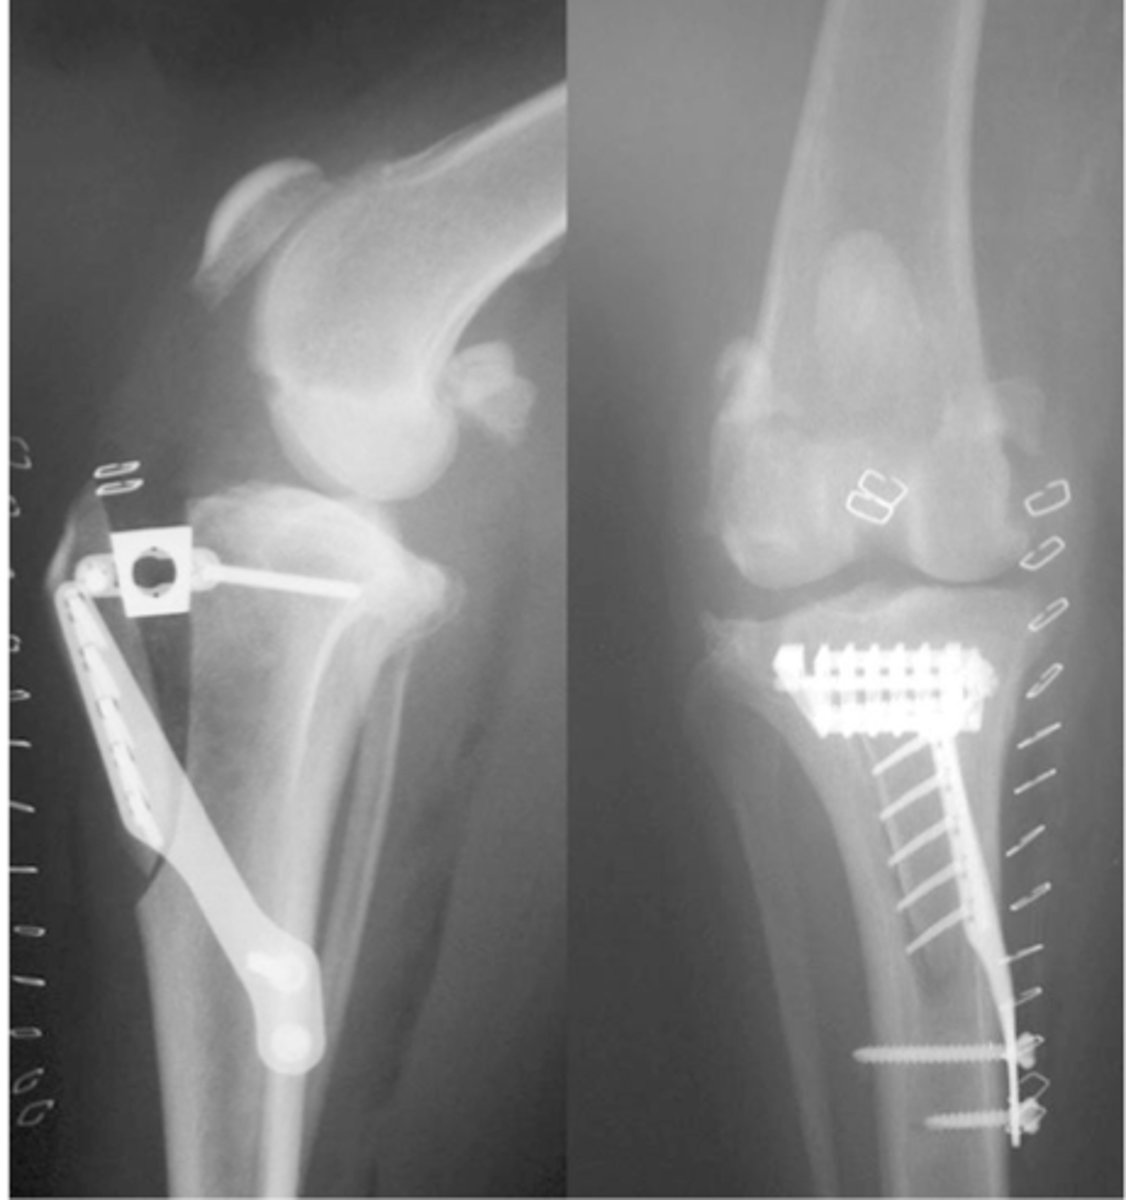

RADs of. TPLO dog to a slope of 5 degrees

what is shown here

RADS for a (TWO) tibial wedge osteotomy dog

post-op RADS of TTA